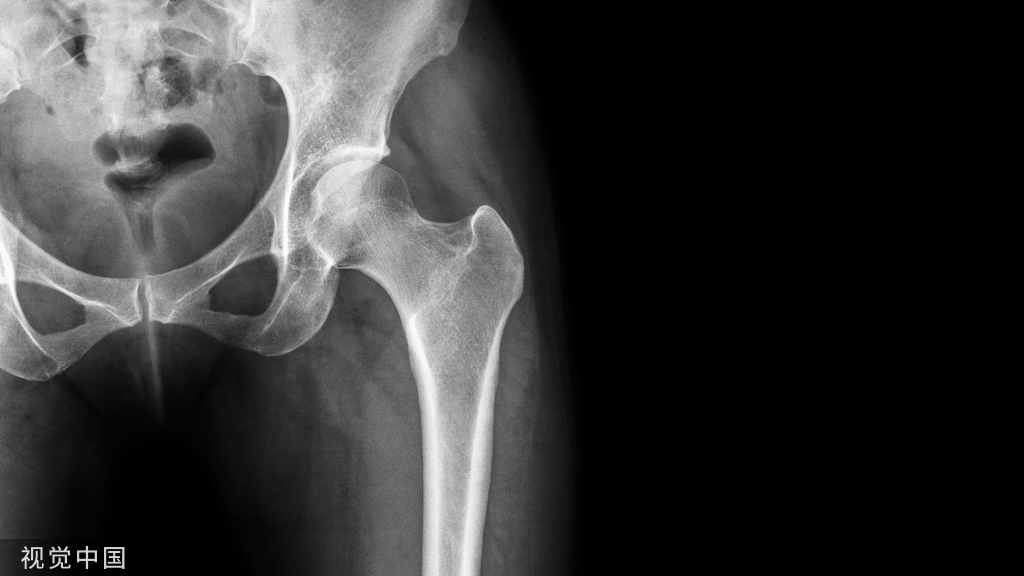

临床上 ,有较多车祸 、高处摔伤等高能量外力引起的胫腓骨、尺桡骨以及肱骨髁上骨折的闭合性损伤以及直接暴力性损伤尤其是挤压伤 ,常常引起较重的软组织损伤 ,容易引发张力性水泡。

骨折发生时,局部软组织(特别是肌肉)也同时受损而出现肿胀,由于皮肤弹性有限,肿胀后皮肤变“紧”,局部压力增加,血管、淋巴管受压,血流回流阻力增加,加之血管受损,毛细血管通透性增加,液体渗出增多,骨折后出血使局部压力更高,渗液在表皮、真皮之间薄弱处积聚形成张力性水泡。骨折后,局部组织损伤程度不同,压力也不均,压力更高处会最先产生张力性水泡。

如果小血管损伤较重,出血明显会形成血泡。血泡表明皮肤全层损伤,提示伤情较重,局部软组织条件差。